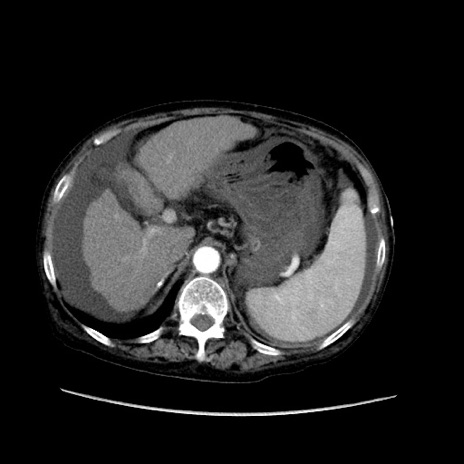

症例31(横断像)

【症例】80歳代 女性

【主訴】腹部膨満感

【現病歴】他院にて肝硬変にてフォロー中。1週間前から便秘、腹部膨満感、臍部腫瘤あり受診となる。

【既往歴】肝硬変

【身体所見】腹部膨隆あり、皮膚変化なし、疼痛なし。

【データ】WBC 4600、CRP 0.25